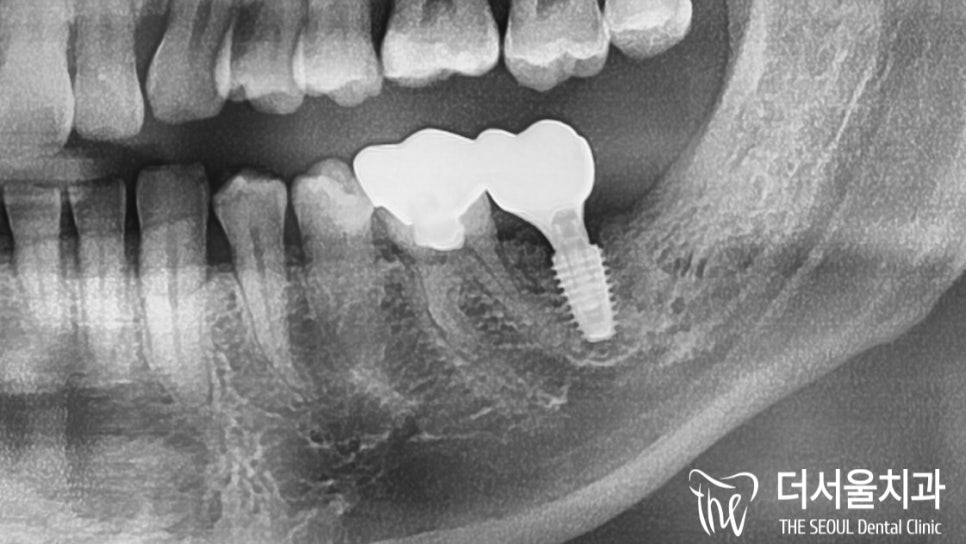

▶ 사랑니 발치

▶ 충치 제거 후 임플란트

두 가지 경우 모두,

하치조 신경관을 조심해서 진행해야 됩니다.

자, 우선 썩어있는 사랑니 와 어금니를

깔끔하게 뽑아주었습니다.

이후, 더서울에서는 컴퓨터 분석을 통해

조직과의 거리, 위치 관계를 파악했습니다.

분석을 통해 결정된 식립로에

픽스처를 단단하게 심어주고

잇몸 형성을 도울 치유지대주까지 결합했습니다.

자, 이제 결과를 공개할 차례네요.

여러 개의 임플란트를 심다가

이렇게 하나만 진료를 하게 되면

더 쉬운 게 아닌가? 생각이 들 수 있는데요.

그러나 고려해야 될 사항들이나

주요 조직들과 가까이 있는 위치 때문에

절대 쉬운 과정은 아니었습니다.

그런데 여기가 어딥니까,

더서울이죠ㅎㅎ

역시나 깔끔하고 튼튼하게 심어졌습니다.